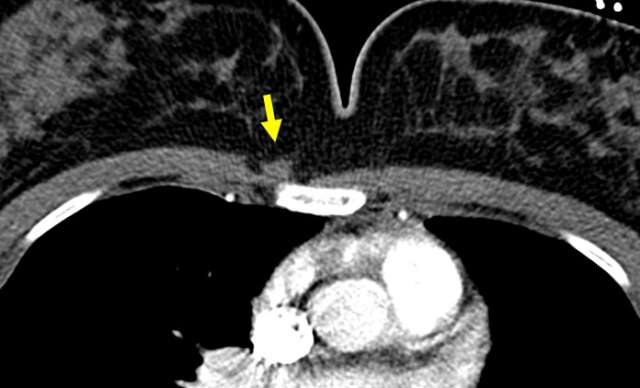

Case Sternalis Muscle Figure 2

Arterial phase contrast enhanced CT of the chest shows a flamed shaped density lateral to the sternum and superficial to the right pectoralis major, consistent with unilateral sternalis muscle. When unilateral, a sternalis muscle is more commonly seen on the right.